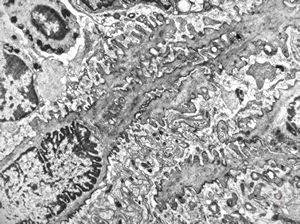

Whipple disease